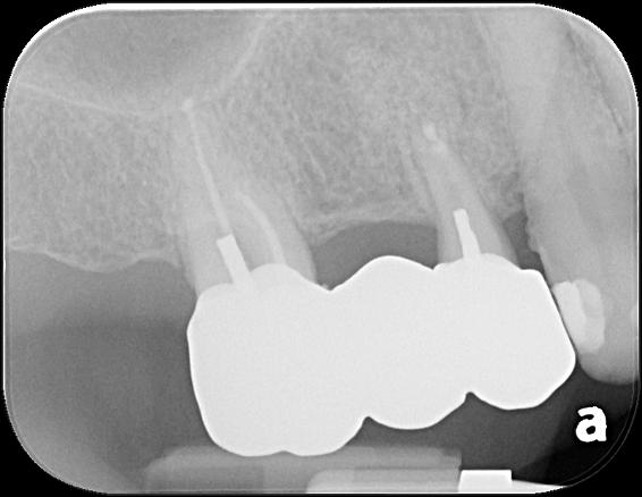

小臼齒顯微根管治療

大臼齒顯微根管治療